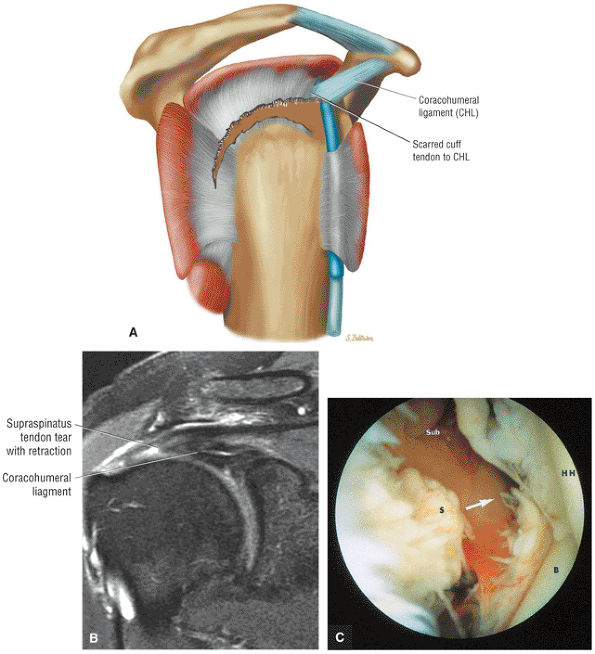

FIGURE 8.102 ● (A) The anterior undersurface of the acromion and the coracoacromial ligament form the coracoacromial arch. The subacromial subdeltoid bursa facilitates the passage of the rotator cuff and proximal humerus under the coracoacromial arch. (B) A superior axial image shows the anterior-to-posterior extent of the coracoacromial (CA) ligament perpendicular to the supraspinatus tendon. The fluid in the subacromial-subdeltoid bursa represents fluid between two serosal surfaces in contact with each other. One serosal surface is contributed by the undersurface of the coracoacromial arch and deltoid, and the other serosal surface is on the bursal side of the cuff.

|

![]() |